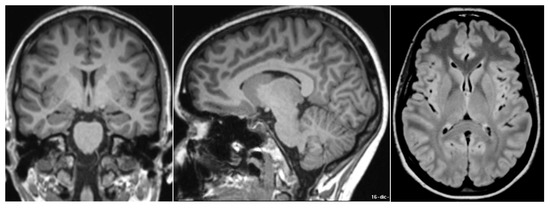

- Sirkis, D.W.; Bonham, L.W.; Johnson, T.P.; La Joie, R.; Yokoyama, J.S. Dissecting the clinical heterogeneity of early-onset Alzheimer’s disease. Mol. Psychiatry 2022, 27, 2674–2688. [Google Scholar] [CrossRef]

- Knopman, D.S.; Amieva, H.; Petersen, R.C.; Chételat, G.; Holtzman, D.M.; Hyman, B.T.; Nixon, R.A.; Jones, D.T. Alzheimer disease. Nat. Rev. Dis. Prim. 2021, 7, 115–140. [Google Scholar] [CrossRef] [PubMed]

- McKhann, G.M.; Knopman, D.S.; Chertkow, H.; Hyman, B.T.; Jack, C.R.; Kawas, C.H.; Klunk, W.E.; Koroshetz, W.J.; Manly, J.J.; Mayeux, R.; et al. The diagnosis of dementia due to Alzheimer’s disease: Recommendations from the National Institute on Aging-Alzheimer’s association workgroups on diagnostic guidelines for Alzheimer’s disease. Alzheimers Dement. J. Alzheimers Assoc. 2011, 7, 263–269. [Google Scholar] [CrossRef]

- Herholz, K.; Salmon, E.; Perani, D.; Baron, J.-C.; Holthoff, V.; Frölich, L.; Schönknecht, P.; Ito, K.; Mielke, R.; Kalbe, E. Discrimination between Alzheimer Dementia and Controls by Automated Analysis of Multicenter FDG PET. Neuroimage 2002, 17, 302–316. [Google Scholar] [CrossRef]